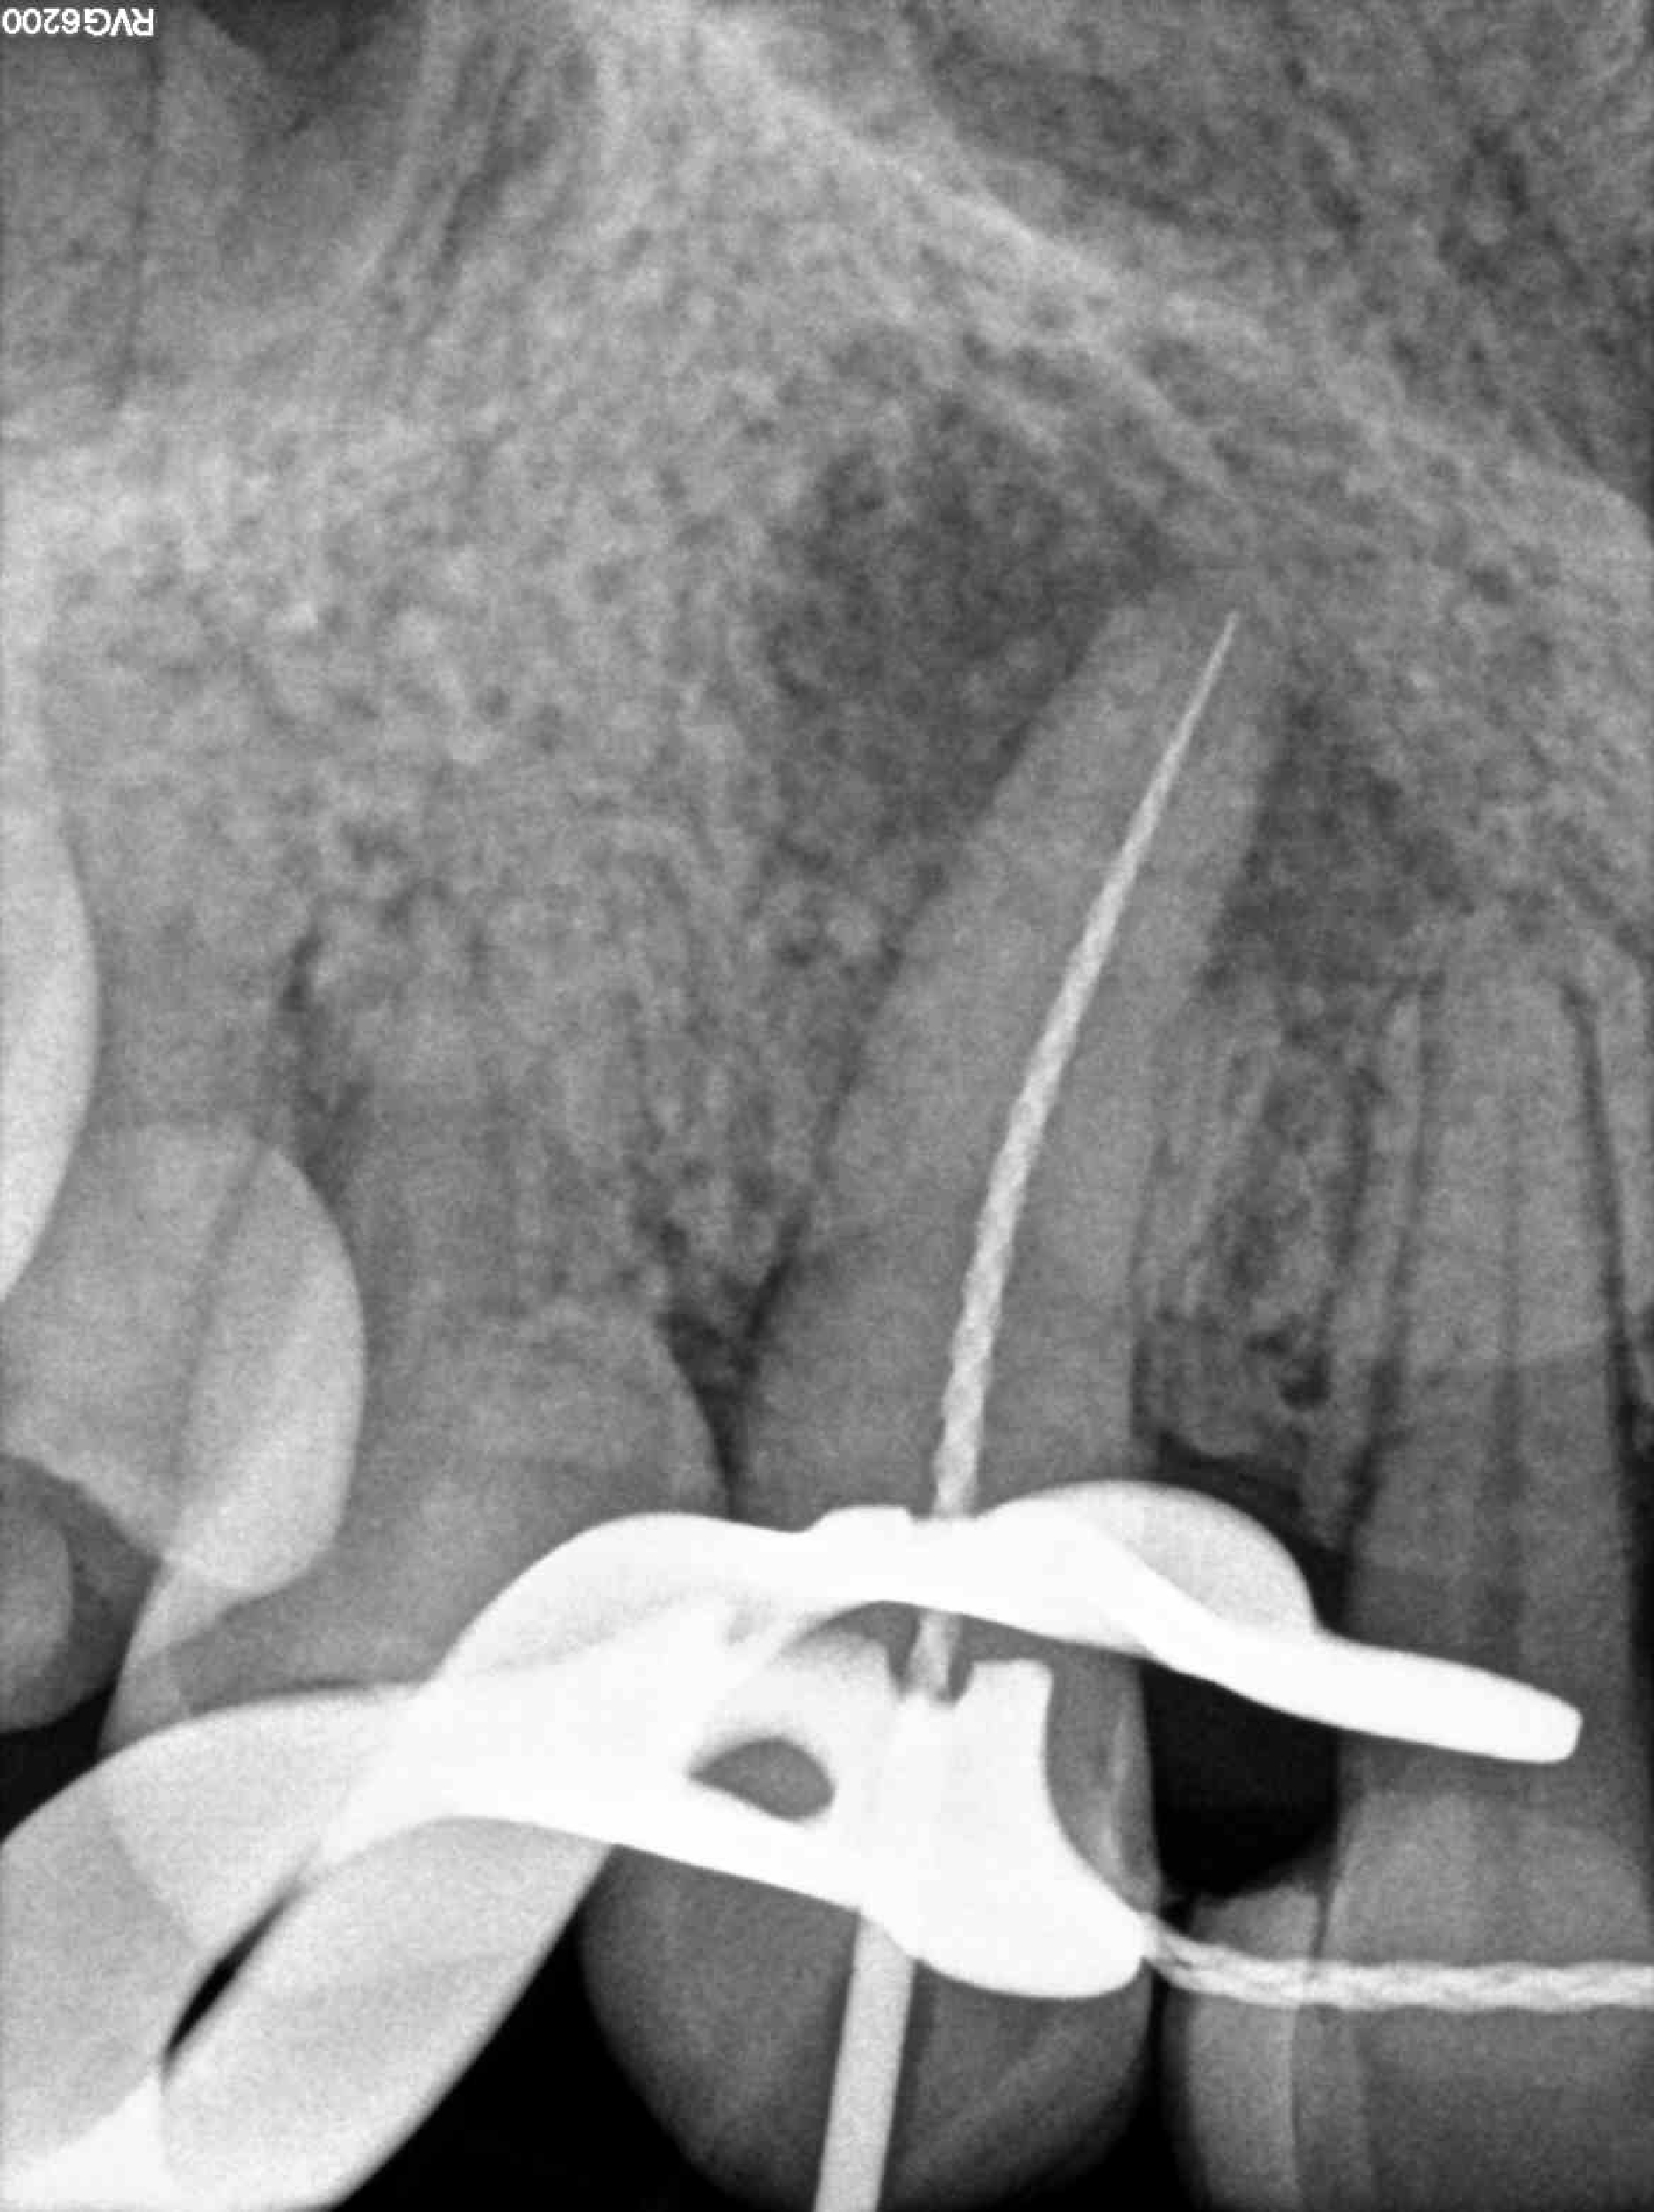

Radiografías

* Haz click sobre las radiografías para verlas a mayor tamaño